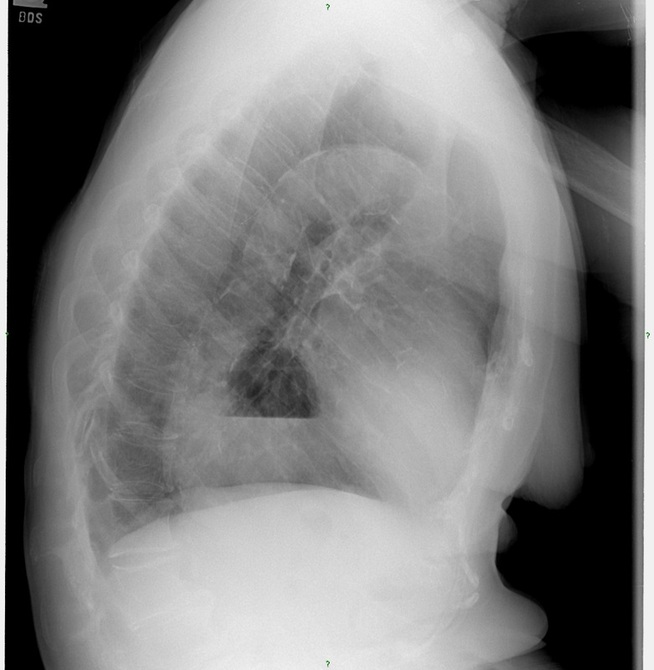

1. Describe the main finding.

Key finding is the presence of a mass overlapping the cardiac shadow. A key finding which can help direct you to the diagnosis is the presence of an air-fluid level in the opacity.

2. Do you have a diagnosis or a differential diagnosis?

Differentials for an opacity overlying the cardiac shadow include aortic aneurysm, neoplasm, abscess, dilated esophagus, and hiatal hernia. If you caught the air-fluid level this helps narrow your differential diagnosis list. (see below for answer)

3. What additional view would you like to see to help narrow your differential list or to make the diagnosis?

A lateral view can help confirm your diagnosis or narrow your differential. In some cases where the lateral view does not provide additional information then a barium swallow or CT may be needed to confirm the diagnosis.